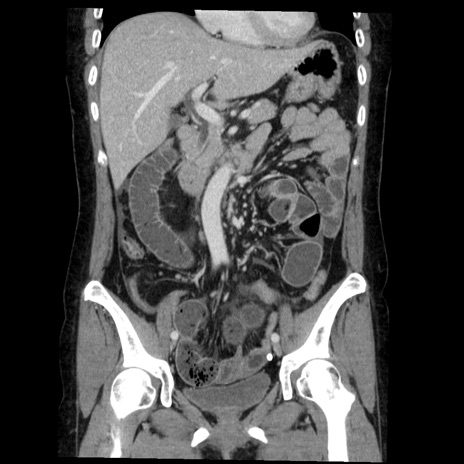

症例6(冠状断像)

【症例】50歳代女性

【主訴】下腹部痛

【現病歴】本日朝より下痢2回あり。 昼食を食べた後、嘔吐3回、下腹部痛認め、症状軽快せず、当院救急搬送。

最終食事:本日昼(生ものなし)。 昨日の夜、刺身を食ぺたとのこと。周囲に同様の症状の者なし。普段、排便は毎日あるとのこと。

【既往歴】卵巣癌術後(8年前に当院で卵巣摘出)

【身体所見】 意識清明、腹部:平坦、腸蠕動音→、やや硬、下腹部自発痛・圧痛あり、反跳痛あり、筋性防御なし。

【データ】WBC 16000、CRP 0.01